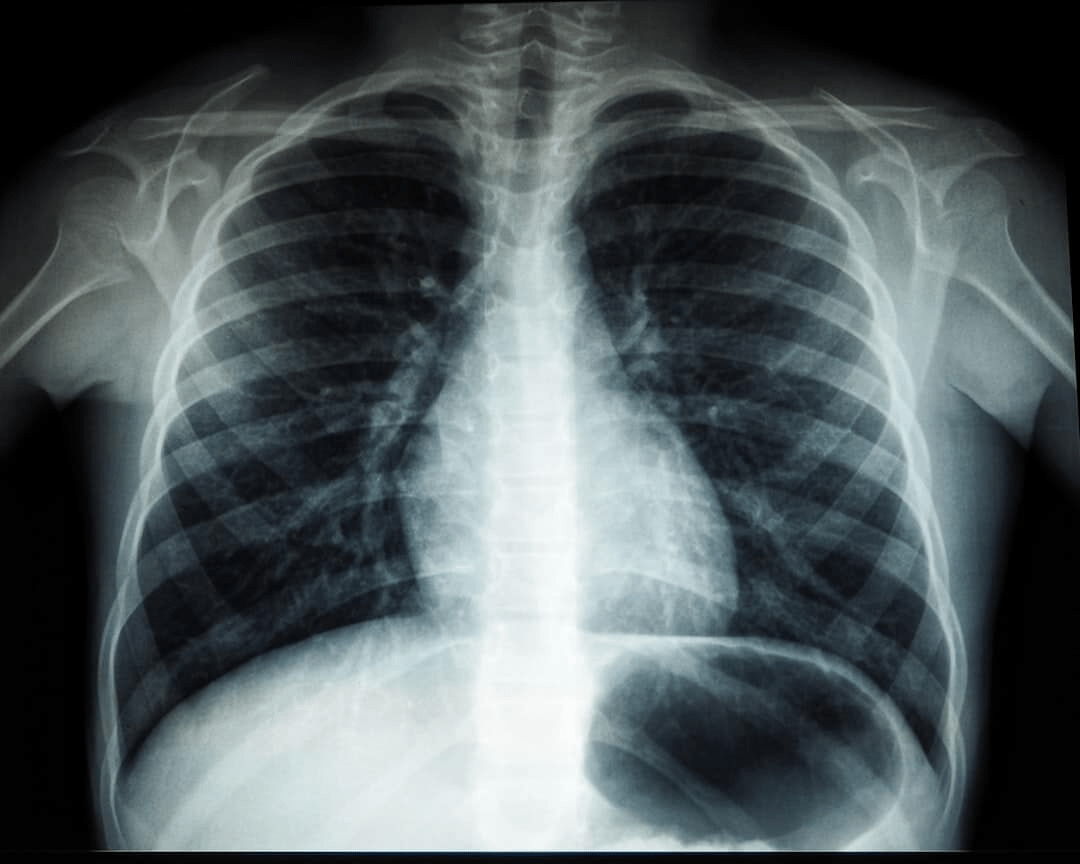

O principal exame para detectar a siderose é a radiografia de tórax. O acúmulo de partículas de ferro aparece como pequenas manchas opacas nos pulmões, que são visíveis em exames de imagem. Devido ao fato de os sintomas demorarem a aparecer, muitas vezes o diagnóstico só acontece durante exames de rotina.